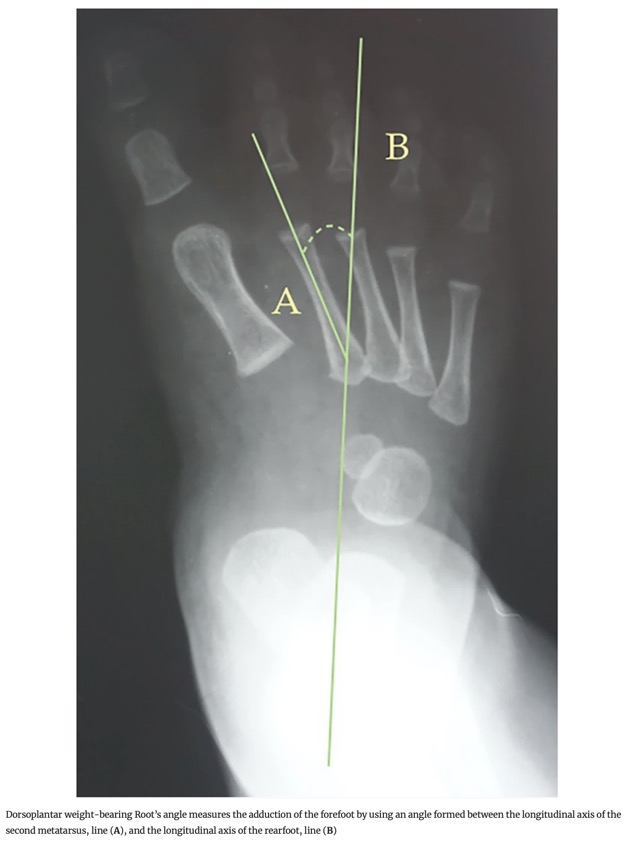

- 5. Angle de Root : Angle entre l'axe longitudinal du deuxième métatarsien et l'axe longitudinal de l'arrière-pied.